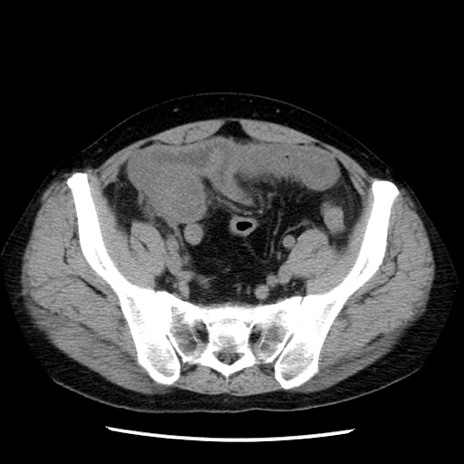

症例29(横断像)

【症例】40歳代男性

【現病歴】2日前から胃痛あり。徐々に周期的な激痛に変化した。本日になっても激痛があるため受診。

【身体所見】意識清明、BT 38-39℃台あり、腹部:膨満、やや硬、右下腹部に圧痛あり。

【データ】WBC 8500、CRP 23.26